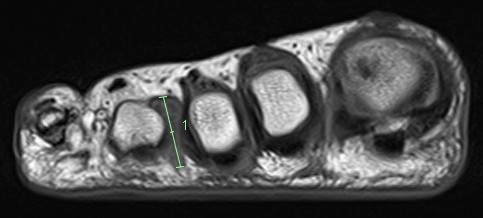

MRI

Obliteration of fat pad

Dumbbell shaped lesion between metatarsal heads

Mortonmorton

Morton's neuroma 3rd webspace

Mortonsmortons

Morton's neuroma 2nd webspace